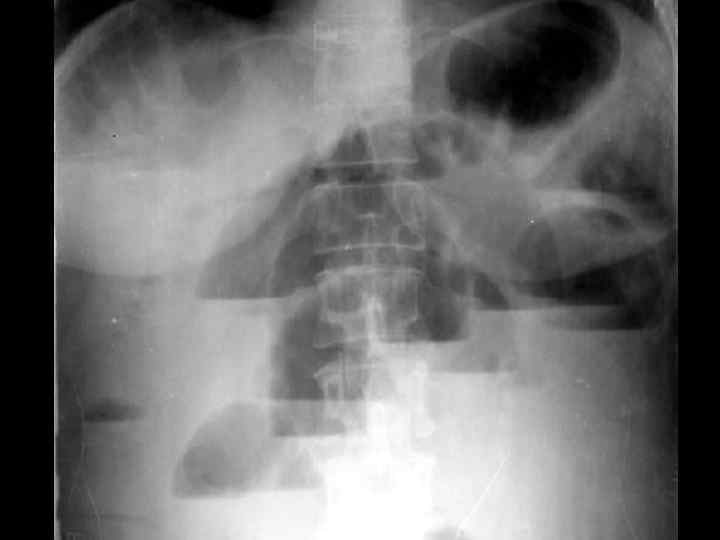

ИРРИГОСКОПИЯ

ОБТУРАЦИОННАЯ ТОЛСТОКИШЕЧНАЯ НЕПРОХОДИМОСТЬ • • опухолевый анамнез возраст больных схваткообразные боли в животе задержка стула и газов "поздняя" рвота вздутие живота интоксикация Симптомы Цеге–Мантейфеля, Обуховской больницы • при рентгенографии- множественные толсто- и тонкокишечные уровни, пневматоз толстой кишки